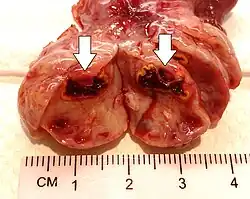

Corpus luteum cyst

A corpus luteum cyst or luteal cyst is a type of ovarian cyst which may rupture about the time of menstruation, and take up to three months to disappear entirely. A corpus luteum cyst does not often occur in women over the age of 50, because eggs are no longer being released after menopause. Corpus luteum cysts may contain blood and other fluids. The physical shape of a corpus luteum cyst may appear as an enlargement of the ovary itself, rather than a distinct mass-like growth on the surface of the ovary.

This type of functional cyst occurs after an egg has been released from a follicle. The follicle then becomes a secretory gland that is known as the corpus luteum. The ruptured follicle begins producing large quantities of estrogen and progesterone in preparation for conception. If a pregnancy doesn't occur, the corpus luteum usually breaks down and disappears. It may, however, fill with fluid or blood, causing the corpus luteum to expand into a cyst, and stay in the ovary. Usually, this cyst is on only one side, and does not produce any symptoms.[1][2]